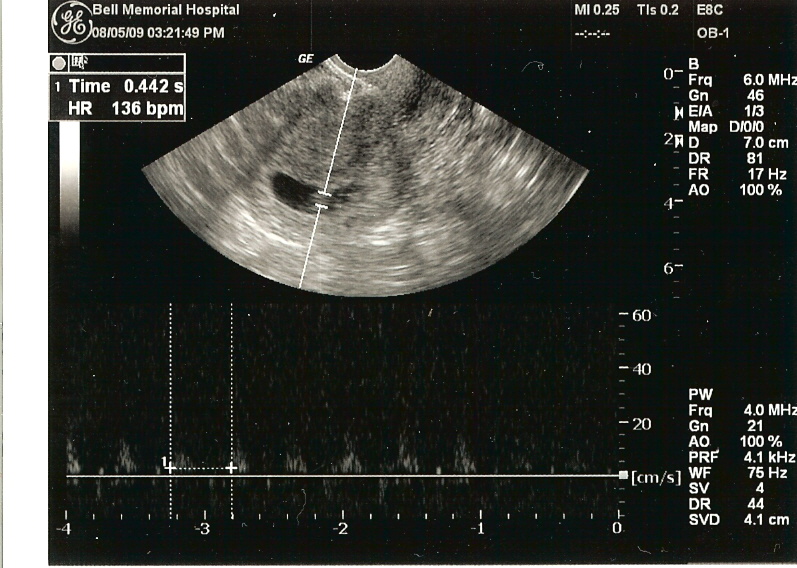

Hi, my name is Samuel Ezra Salo! I was in my Mommy's tummy for quite awhile. I got out of her tummy on March 17, 2010 at 4:54pm. (I didn't have my watch on so I cannot confirm the time.) Daddy and Mommy tell others I was 10 pounds 3 ounces and was 21 1/2 inches long when I came out of my Mommy's tummy. I don't know what that means but will probably figure out someday. For now I will just hang out with Daddy and Mommy.